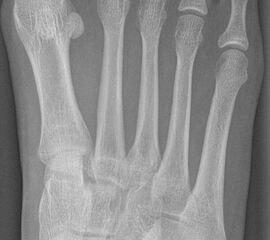

Schneiderballen: MT V Osteotomie

Diese Osteotomie ist indiziert bei stark lateralisierten MT V Köpfchen wie es nicht selten in Kombination mit einem Hallux valgus, einem Ballen-Hohlfuß oder Klumpfuß vorkommt (Abb. 25).

Abb. 25: Prominentes MT V Köpfchen, eine sogenannte Schneiderballen-Deformität.

Dementsprechend führen wir die MT V Osteotomie häufig als Kombinationseingriff durch. Sie kann subcapital im Sinne der Kramer-Osteotomie oder adduzierend am Schaft durchgeführt werden (Abb. 26).